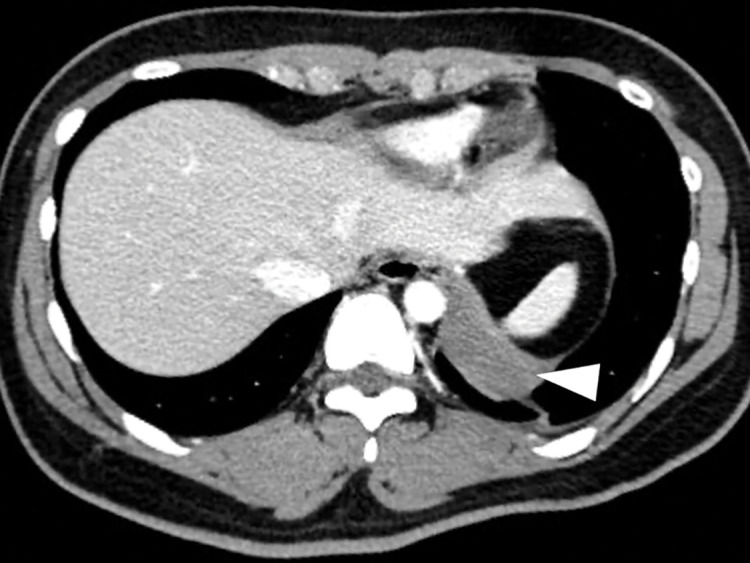

Case presentation: An 18-year-old female presented with a fever and sudden left-sided back pain. Blood tests revealed leukocytosis and an elevated C-reactive protein. Imaging studies identified a well-circumscribed cyst along the left diaphragm, suspected to be an infected bronchogenic cyst. Magnetic resonance imaging 2 days later indicated disease progression with concomitant empyema, prompting emergency surgery. Using the confronting upside-down monitor setting, the cyst was resected. Thoracoscopic findings revealed a dark red cyst and bloody pleural effusion. The surgery was uneventful, and the patient was discharged on postoperative day 2. Bacterial cultures of the pleural effusion and cystic content were negative, and histopathological analysis confirmed the diagnosis of a hemorrhagic bronchogenic cyst.